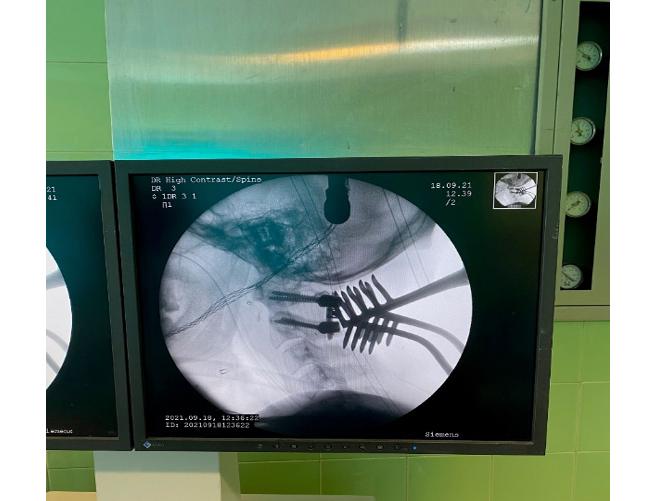

Under general anesthesia, the patient was placed in the supine position. Under fluoroscopy guide and C-ARM imaging monitoring, several times of closed reductions were attempted through gradual manual cranial traction from flexion to extension (Figure-2). To sum up the surgery process; we can say that three phases were done, first of all, the flexion of the head and neck with traction was done, then neutral position applied when the odontoid process was near the posterior wall of the anterior C1 arch. During the process, the odontoid process was locked in the inferior of the anterior C1 arch. Therefore, in the 3rd phase, we decided to push back the odontoid process by using an impactor (Figure-3) through the retro pharynx. The maneuver was successful, and the odontoid was placed in its position. All phases were done under neuromonitoring. Then, He was positioned from supine to prone to fix the C1 and C2 vertebrae. We exposed the axis and atlas surgically via a posterior approach. The attempts to relocate the normal axis-atlas alignment to fuse the facet joints failed. The lateral mass screw was applied for C1, and pedicular 24*8 mm in the right part of C2 and 26*8 mm in the left one was used. The fusion was applied to reduce the ligament injuries (Figure-4 and 5).

Figure 2. the patient under general anesthesia for an external reduction maneuver